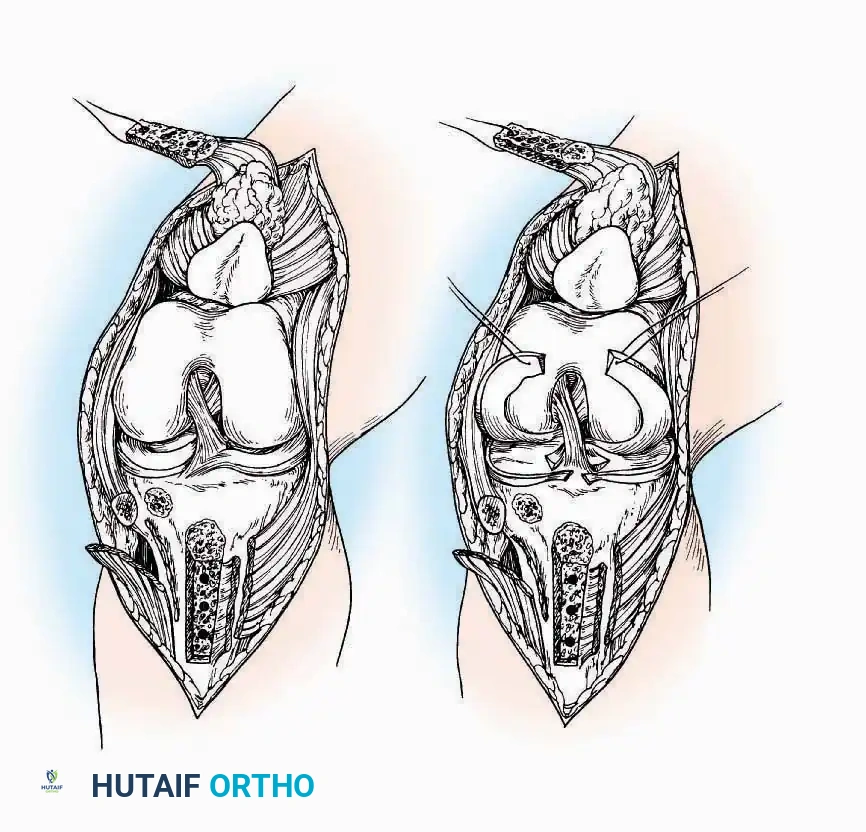

Anterolateral Approach

The anterolateral approach is widely considered the "universal incision" for the foot and ankle. It provides unparalleled access to the ankle joint, the talus, and the majority of the tarsal articulations, while safely avoiding the major anterior neurovascular bundle. The only tarsal joints inaccessible via this route are the naviculocuneiform joints (specifically the medial and intermediate).

Indications: Total talectomy, triple arthrodesis, ankle arthrodesis, and open reduction of complex talar neck fractures.

Surgical Technique:

* Incision: Begin over the anterolateral aspect of the leg, medial to the fibula and 5 cm proximal to the ankle joint line. Carry it distally over the joint, crossing the anterolateral aspect of the talar body and the calcaneocuboid joint, terminating at the base of the fourth metatarsal.

* Superficial Dissection: Incise the superficial fascia and the superior and inferior extensor retinacula down to the periosteum of the tibia and the ankle joint capsule.

* Vascular Ligation: This trajectory usually requires the identification and ligation of the anterolateral malleolar and lateral tarsal arteries.

* Nerve Protection: Retract the skin edges carefully. Identify and protect the intermediate dorsal cutaneous branches of the superficial peroneal nerve (SPN), which frequently cross the distal aspect of this incision.

* Muscle Management: Identify the origin of the extensor digitorum brevis (EDB) muscle on the lateral calcaneus. Divide it in the direction of its fibers, or detach its origin entirely and reflect it distally to expose the subtalar and calcaneocuboid joints.

* Deep Exposure: Retract the extensor digitorum longus (EDL) tendons, the dorsalis pedis artery, and the deep peroneal nerve (DPN) medially. Incise the anterior ankle capsule to expose the tibiotalar joint.

* Tarsal Exposure: Expose the talonavicular joint by dissecting deep to the extensor tendons and incising its capsule transversely. Continue laterally through the capsule of the calcaneocuboid joint. By excising the fat pad within the sinus tarsi (lateral and inferior to the talar neck), the posterior facet of the subtalar joint is brought into direct view.